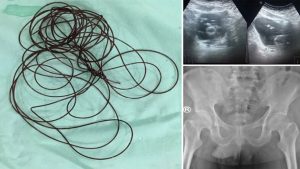

मीडिया रिपोर्ट्स के मुताबिक इस शख्स का नाम नहीं बताया गया है. हालांकि उसने ऐसा क्यों किया इसका खुलासा जरूर हो गया है. पीड़ित ने अस्पताल में कुछ आराम आने के बाद डॉक्टरों को बताया कि एक एडल्ट वीडियो (Adult Video) देखने के दौरान उसने प्राइवेट पार्ट में 2 मीटर लंबा नायलोन का धागा (Nylon thread in private part) डाल लिया था जिसके बाद उसकी मुश्किलें बढ़ गईं. उसने अकेले में बिताए प्राइवेट पलों को रोमांचक बनाने के लिए ऐसा किया.

इस हरकत के दौरान उसे अचानक तेज दर्द होने लगा. उसने बेइज्जती होने की वजह से डॉक्टरों को सच नहीं बताया और ये झूठ बोला कि उसके पेट के निचले हिस्से में दर्द हो रहा है. जब डॉक्टरों ने चेक किया तो पाया कि प्राइवेट पार्ट में 2 मीटर तक लंबा धागा (Man insert 2 meter long thread in private part) डला हुआ है. डॉक्टरों ने बताया कि इस शख्स ने कभी भी संबंध नहीं बनाए थे इसलिए उसके अंदर ऐसा इन चीजों के प्रति ऐसा रवैया था. डॉक्टरों ने बताया कि उसे ऑब्सेसिव कंप्लसिव डिसऑर्डर है.